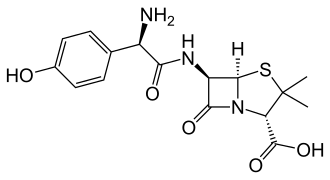

Amoxicillin/clavulanic acid

| Combination of | |

| Amoxicillin | Penicillin antibiotic |

| Clavulanic acid | Beta-lactamase inhibitor |

Amoxicillin/clavulanic acid, also known as co-amoxiclav, is an antibiotic useful for the treatment of a number of bacterial infections.[2] It is a combination consisting of amoxicillin, a β-lactam antibiotic, and potassium clavulanate, a β-lactamase inhibitor.[2] It is specifically used for otitis media, strep throat, pneumonia, cellulitis, urinary tract infections, and animal bites.[2] It is taken by mouth or by injection into a vein.[3]